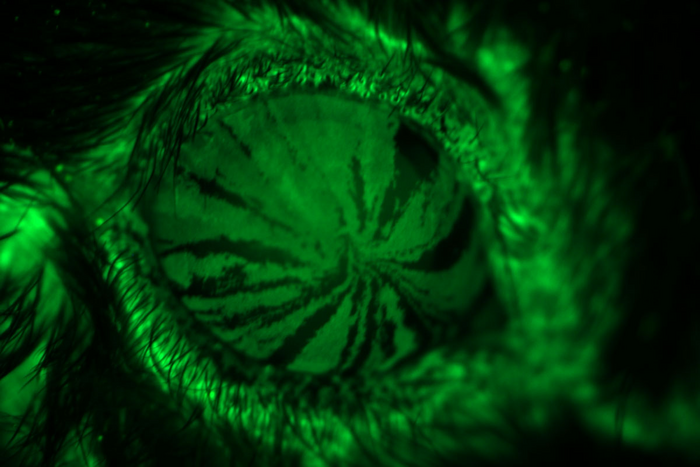

eyes